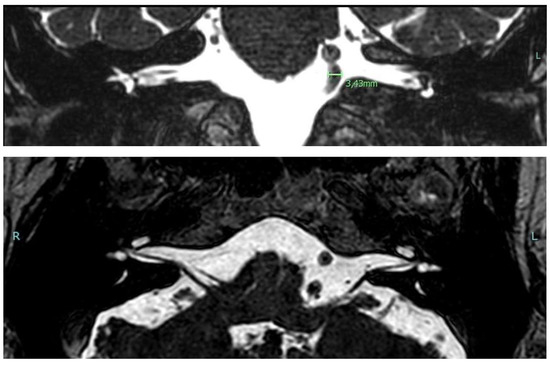

3.1.1. Case 1

3.1.2. Case 2

3.1.3. Case 3